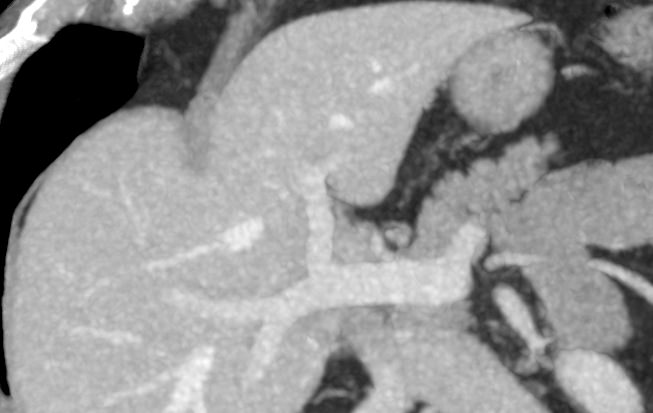

Мультиспиральная компьютерная томография с внутривенным болюсным контрастированием является наиболее точным и информативным методом диагностики патологии воротной вены. КТ основана на применении ионизирующего излучения и способности органов и тканей в разной степени поглощать рентгеновские лучи.

Для улучшения визуализации сосудистого русла пациенту внутривенно вводится йодсодержащий контрастный препарат. Рентгеновские лучи активно поглощаются контрастным веществом, поэтому на снимках хорошо видна сосудистая система воротной вены.

На снимках и трехмерных изображениях хорошо контрастируется сосудистая система воротной вены, участки сужения, визуализируются тромбы в просвете вены, также сеть коллатеральных сосудов, варикозно расширенные вены.